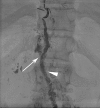

Chylous leaks, such as chylothorax and chylopericardium, are uncommon effusions resulting from the leakage of intestinal lymphatic fluid from the thoracic duct (TD) and its tributaries, or intestinal lymphatic ducts. The cause can be either traumatic (thoracic surgery) or nontraumatic (idiopathic, malignancy). Treatment has traditionally consisted of dietary modification (nonfat diet) and/or surgery (TD ligation, pleurodesis). Thoracic duct embolization (TDE) has become a viable treatment alternative due to it high success rate and minimal complications. In this article, the authors describe the etiologies of chylothorax, patient population, outcomes, and long-term follow-up of TDE patients. Relevant lymphatic anatomy and physiology are reviewed, with special attention paid to the formation of the duct by tributaries at the cisterna chyli (CC). The technique of TDE is outlined, including bilateral pedal lymphangiography, TD cannulation, and embolic agents used for the procedure.